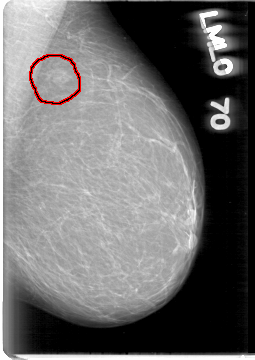

D_4003_1.LEFT_MLO

LEFT_CC LINES 5191 PIXELS_PER_LINE 3346 BITS_PER_PIXEL 12 RESOLUTION 43.5 OVERLAY

FILE: D_4003_1.LEFT_CC.OVERLAY

TOTAL_ABNORMALITIES 1

ABNORMALITY 1

LESION_TYPE MASS SHAPE IRREGULAR MARGINS OBSCURED

ASSESSMENT 0

SUBTLETY 4

PATHOLOGY BENIGN

TOTAL_OUTLINES 1

BOUNDARY